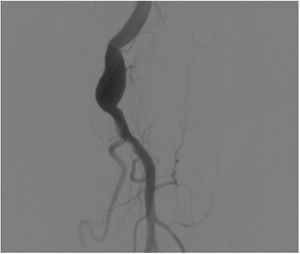

Doppler ultrasound of the left upper limb showed a partially thrombosed brachial artery aneurysm with a length of 25mm. An arteriogram showed a fusiform aneurysm in the brachial artery at the level of the elbow joint. The radial and ulnar arteries, as well as the deep palmar arch, were patent. The digital arteries of the thumb, index and middle fingers were patent, and occlusion, probably embolic, of the digital arteries corresponding to the 4th and 5th fingers was seen. Ligation and resection of the aneurysm was performed, and a brachial to radial bypass was carried out (Fig. 2).